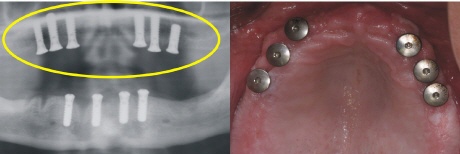

Ausgangssituation

Das Bild rechts zeigt den zahnlosen Oberkiefer. Im Röntgenbild sieht dies aus wie auf dem linken Bild (gelber Kreise).